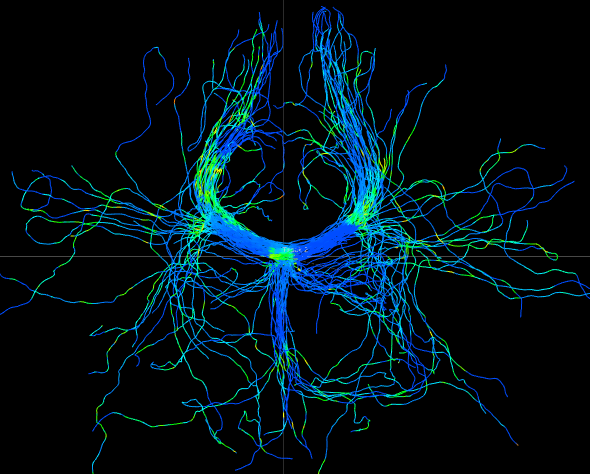

We perform whole brain streamline tractography on the estimated fODF field using mrtrix (Tournier et al., 2012) 888http://www.mrtrix.org/. The voxels with GFA larger than are used as seed voxels to generate tracts by using tckgen in mrtrix. All other parameters are default parameters in mrtrix. The obtained fiber tracts are then visualized by using trackvis 999http://trackvis.org. Fig. 14 and 15 demonstrate the tracts respectively cross two given ball ROIs. The tracts are colored by using the proposed six scalar indices. Note that the proposed scalar indices are calculated based on estimated fODFs, not based on fiber tracts. It can be seen that 1) OO is high in areas with well aligned fibers, while OD is high in crossing areas and distortion areas; 2) distortion indices are low when fibers are well aligned; 3) the total distortion index is high in areas with highly curved fibers or crossing fibers. 4) although splay, bend, twist indices may be separable (e.g., one is large while another one is close to zero) in synthetic data, in real data, these three types of distortions normally occur together, especially for bending and splaying. 5) the ROI in Fig. 14 is the crossing area of the Corpus Callosum and the Fornix, where all distortion indices have high values, especially for twist and total distortion indices. This finding agrees with Fig. 12.